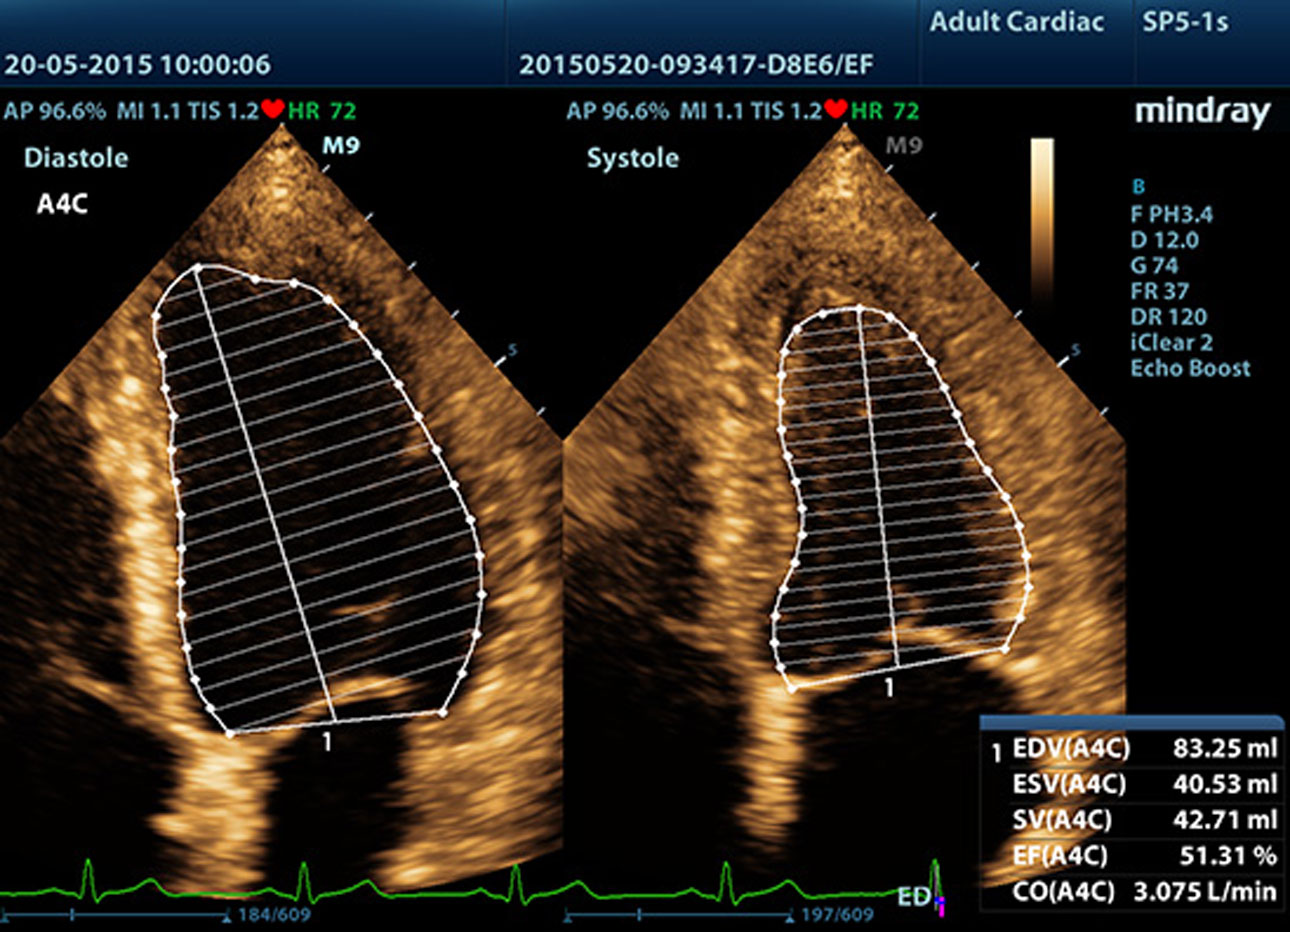

Auto LV

Procedimiento de medici├│n simple del ventr├Łculo izquierdo mejorado gracias a la funci├│n de seguimiento autom├Ītico y f├Īcil correcci├│n manual.

Fracci├│n de eyecci├│n autom├Ītica (AutoEF)

Una forma inteligente de analizar las 2D para reconocer autom├Īticamente los niveles diast├│licos/sist├│licos y generar la estimaci├│n diast├│lica, el volumen diast├│lico, la fracci├│n de eyecci├│n (EDV/ESV/EF), etc. resultantes del m├®todo Simpson.